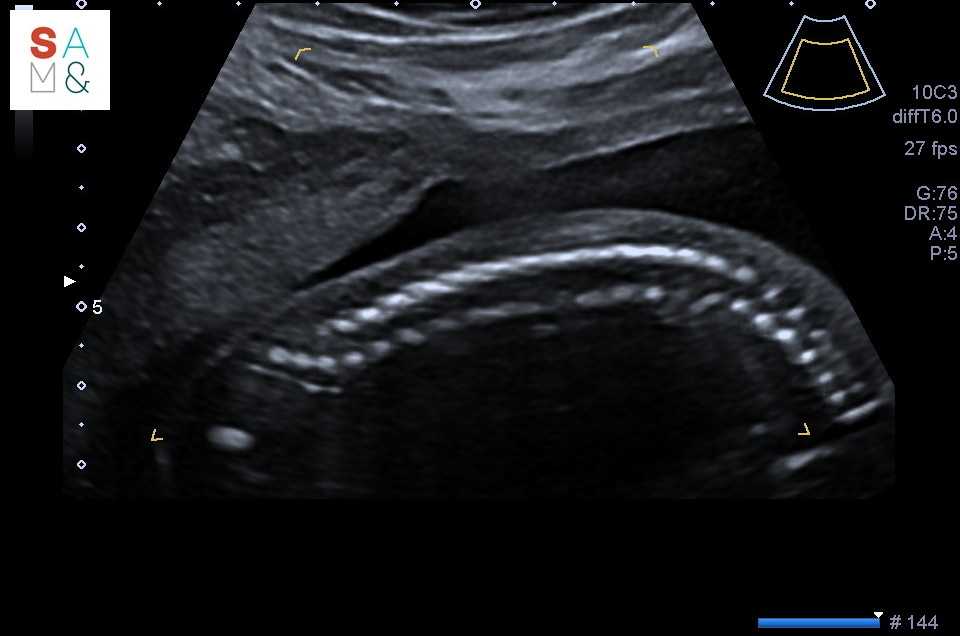

Net de 20 weken echo gehad.

Alles ziet er goed uit, het wordt een gezonde alien!

Ik ben nu al trots.

*die echo is dus echt net gemaakt.

Zie geen flaporen op de echo, dus geen zorgen. Is duidelijk geen afraffelwerk geweest bij het bouwenNet de 20 weken echo gehad.